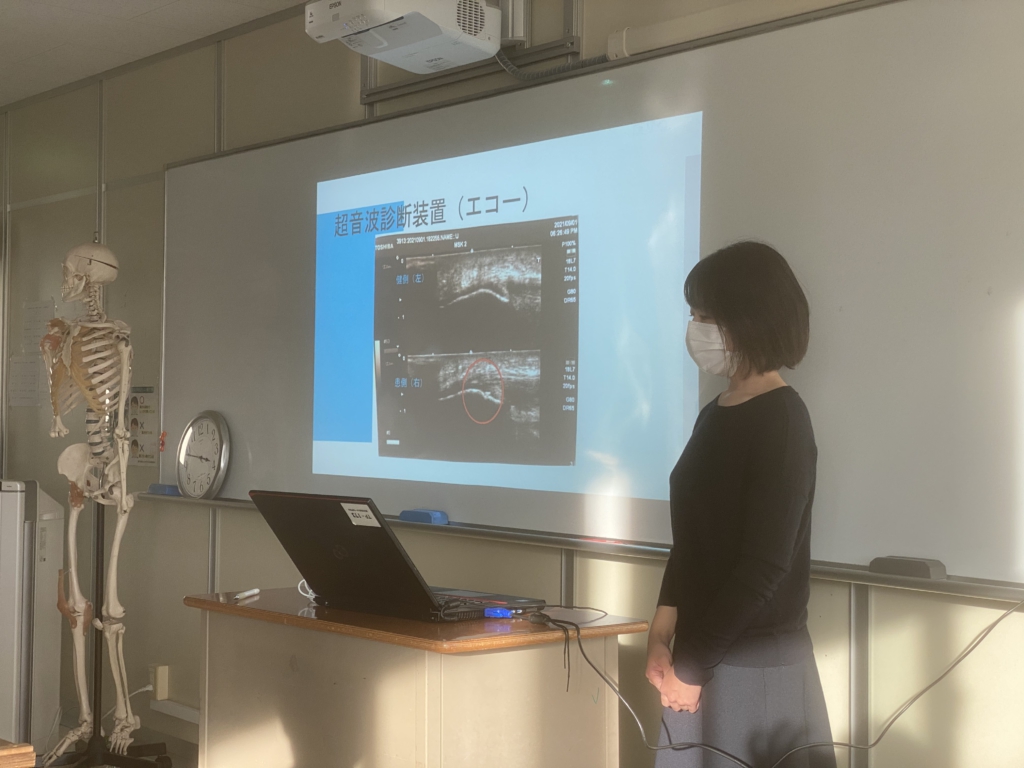

さて、実習期間中のブログでも紹介したが、彼女は超音波エコー観察検査に興味と関心があり、奥田院長自らも複数回、甲子園出場を果たし、現在も甲子園出場経験のある高校でトレーナーをしている、京都かもがわ整骨院(奥田院長)で実習を受けた。その発表風景と症例を紹介しよう。

患者情報は、右膝部の痛みを訴えて来院。17歳男子、高校野球部、178㎝/75㎏、既往歴半年ほど前、右膝蓋腱炎(当院受診)であった。

奥田院長が、超音波エコー観察検査を実施。写真にあるように骨折が確認され、野球のトレーニングによる、右脛骨疲労骨折の疑いありと判断。1か月ほどの安 静と運動禁止、のちに野球運動フォームの修正と改善に向けて指導を行うとの事。

奥田先生が常に実習生に指導されている『症状の原因追及をしないと再発防止に貢献できない』との内容も発表で強調し、スポーツ障害はそこが重要であると強調していた事は、実習を通じて彼女の成長につながり、将来スポーツ損傷を治療する重要な指標となるだろう。

実習の経験を上手にまとめ、良く研究された発表でした。